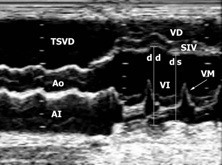

Stacks Image 3265

Ecocardiografía modo M. Severa dilatación de los diámetros diastólicos (dd) y sistólicos (ds) del ventrículo izquierdo (VI) con pobre contractilidad.